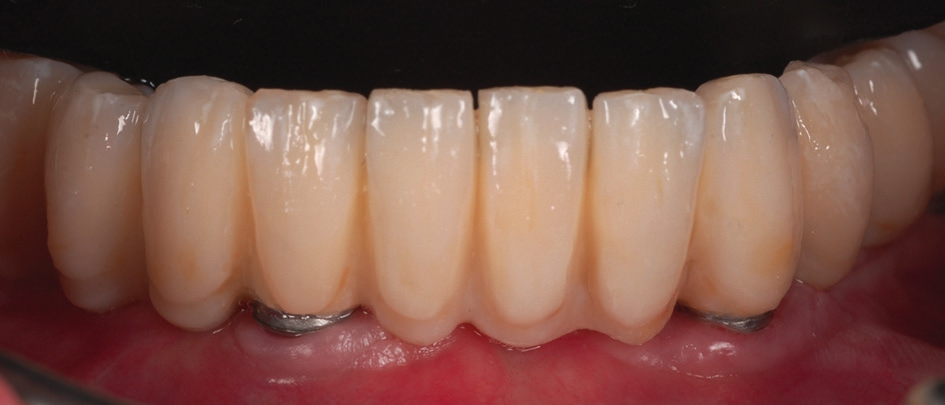

Als dritte Behandlungsoption wurde eine bedingt herausnehmbare Rekonstruktion gewählt, die auf den systemeigenen PS MultiPlus-Abutments befestigt wurde (Abb. 16 und 17). Grundlage für die bedingt herausnehmbare Brücke war ein mittels Selective Laser Melting hergestelltes Kobalt-Chrom Gerüst (EOS; Electro Optical Systems München, Deutschland). In unserem Patientenfall konnte eine sehr gute, passgenaue Herstellung des Metallgerüsts erfolgen (Abb. 18). Das Gerüst wurde mittels Komposit (anaxblend big block dentin und big block enamel, anaxdent GmbH, Stuttgart, Deutschland) verblendet (Abb. 19a und b). Die Schraubenkanäle wurden nach Einsetzen der Suprakonstruktion mit Komposite (EcuSphere-Carat, DMG Chemisch- Pharmazeutische Fabrik GmbH, Hamburg, Deutschland) verschlossen (Abb. 20). Das klinische Endergebnis war für den Patienten sehr zufriedenstellend, da die Rekonstruktion sehr natürlich und ästhetisch gestaltet war (Abb. 21).